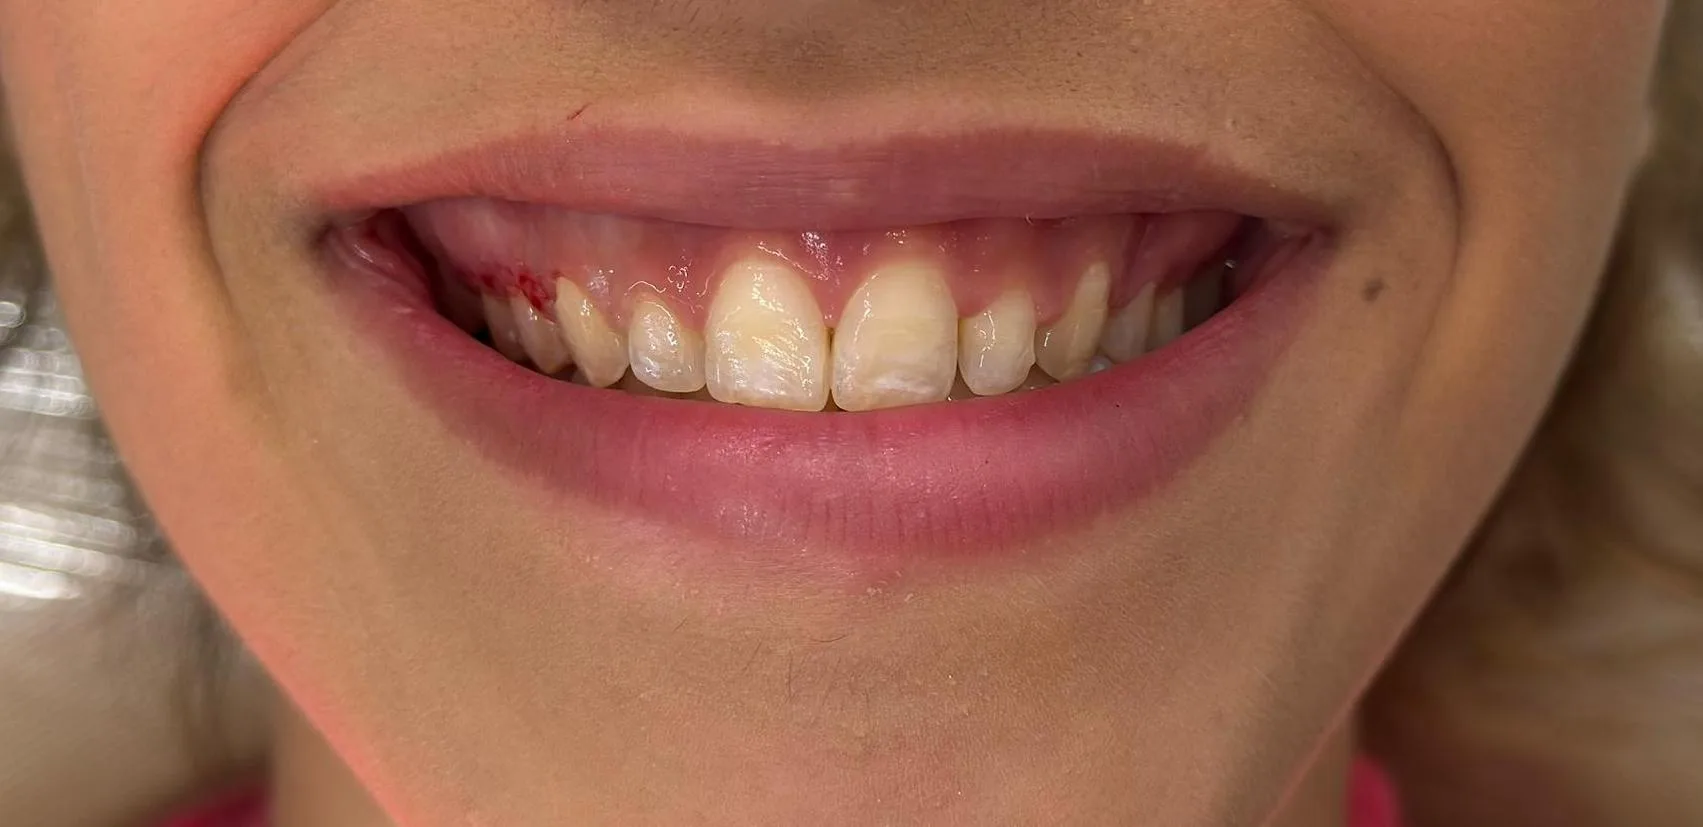

Caso 04

Gengivoplastia - Estética Vermelha

Antes

Antes

Depois

Depois